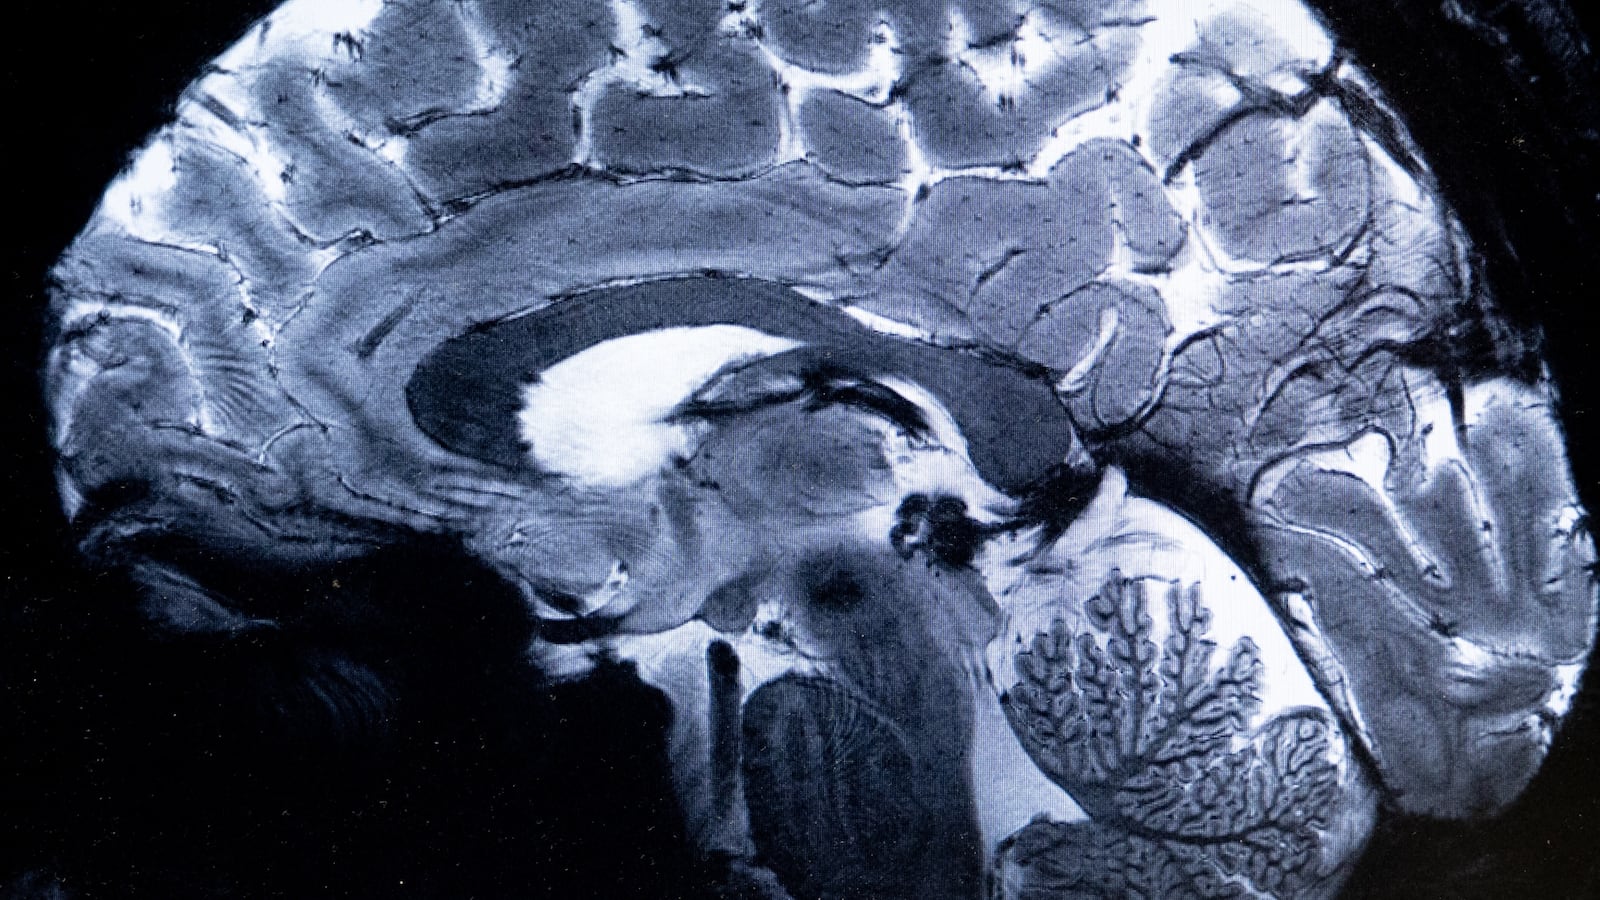

A new study has found that adolescence doesn’t just last through our teens and early twenties, but in fact continues into our early thirties. Researchers at the University of Cambridge studied the brain scans of 4,000 people and discovered the brain goes through five distinct phases in life: childhood from birth to age 9, adolescence from age 9 to 32, adulthood from age 32 to 66, early aging from 66 to 83, and late aging from 83 onwards. During the adolescent phase, the brain’s connections undergo the biggest shift, becoming far more efficient but also more susceptible to the onset of mental health disorders. The brain then “peaks” at about age 32 and enters a period of stability—adulthood—that represents its longest era. During adulthood, intelligence and personality plateau, until connections in the brain begin changing again around age 66. At that point, the brain’s individual organs become increasingly separated into regions that work closely together, instead of coordinating across the whole brain.